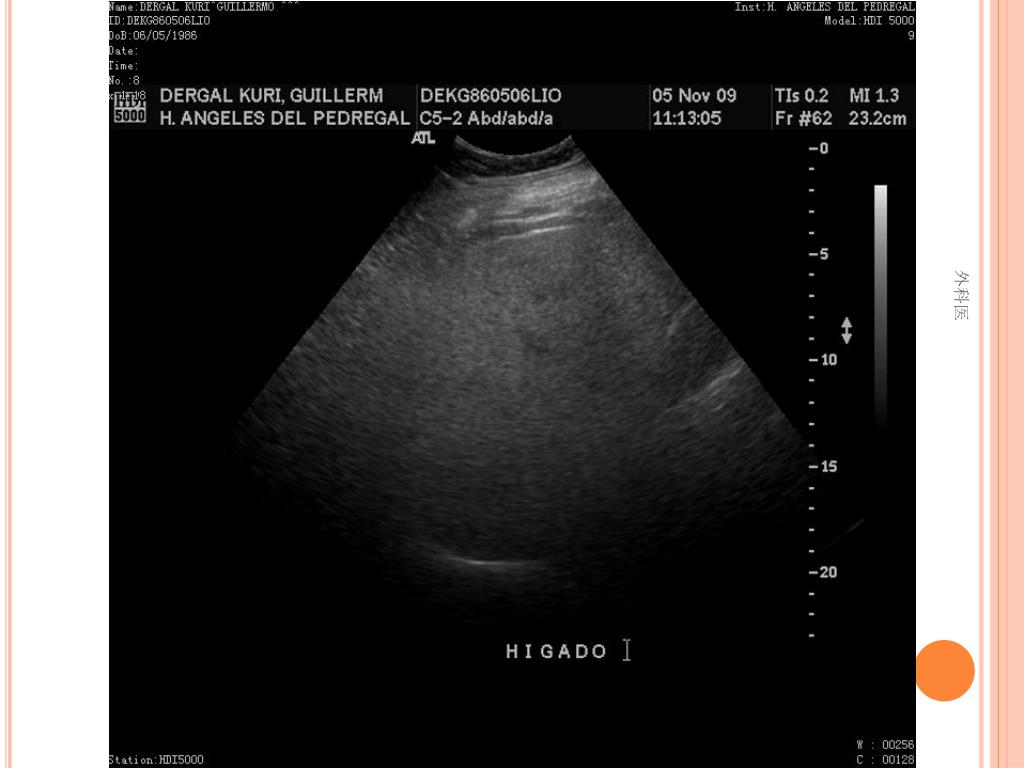

44. Tips • Leucocitos Mas de 20000/ml • Mas de 20% de la apéndices no se llenan con el bario por enema. • USG sensibilidad del 85% y Especificidad de mas 90% para Apendicitis Aguda. • TAC de Abdomen cortes de 5mm, sensibilidad y especificidad del 90% para dolor abdominal. • Analisis de 75000, taza de apendice negativa de 6% Hombres y 13% Mujeres 外科医